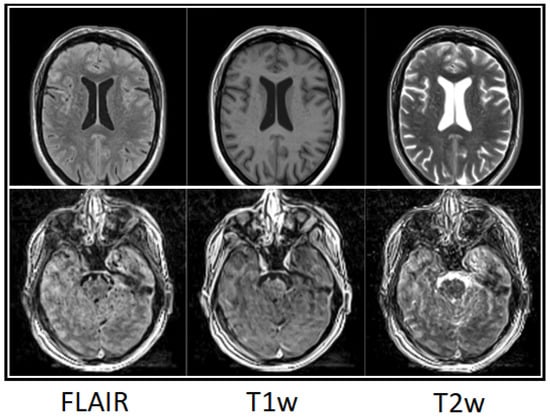

Clinical Image Quality and Reader Variability in 3D Synthetic Brain MRI Compared with Conventional MRI

Background/Objectives: This study evaluated the clinical image quality of three-dimensional synthetic MRI (3D SI) compared with conventional MRI (cMRI), focusing on tissue contrast, anatomical detail, and motion sensitivity. Methods: Patients with nonspecific neurological symptoms were included. Both cMRI and 3D SI were acquired on single-vendor 1.5 T and 3 T scanners with slice thicknesses of 1.0–1.7 mm. Two experienced neuroradiologists and one fellow independently evaluated matched scans using a 0–100 scale. Assessed parameters included signal-to-noise ratio (SNR), gray–white matter contrast, artifacts, motion robustness, and confidence in detecting perivascular spaces, white matter lesions, and subtle pathology. Interrater agreement was measured using Krippendorff’s alpha and ICC2. Multiple linear regression analyzed associations between image quality ratings and imaging method. Results: Images of 31 patients were analyzed. Three-dimensional SI demonstrated sufficient-to-good overall image quality and high robustness to motion. Cortical-surface-to-cerebrospinal-fluid contrast on FLAIR was rated lower for 3D SI than for cMRI. False-positive lesion detection occurred more frequently on 3D SI FLAIR, particularly among experienced readers. cMRI achieved significantly higher T1-weighted SNR than 3D SI (8.76 points, p < 0.001). Experienced readers consistently rated SNR and tissue contrast higher than the fellow. Vascular signal range was broader on 3D SI, reducing sensitivity to vascular abnormalities. Conclusions: Three-dimensional synthetic MRI provides clinically usable image quality and fulfills its primary diagnostic purpose, offering advantages in acquisition efficiency and robustness to motion. Nevertheless, limitations in cortical contrast, vascular signal characterization, and reader-dependent interpretive variability constrain its reliability for subtle or detail-critical findings. Full article